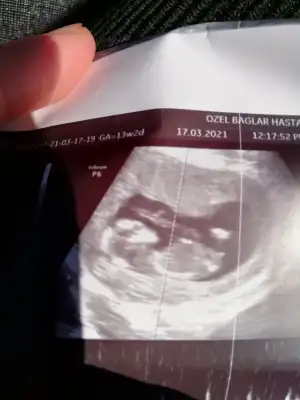

Ikra meyra Ikra meyra tahminin doğru çıktı 16 hafta erkek demiştin doktorum kesin erkek elbiselerini bile al dedi ☺ değişir mi bilmiyorum ama atıyim bir bak

Artık erkektir canım 😍 sağlıkla gelsin oğlusun 🥰 anketim oylarsaniz sevinirim 😘